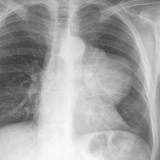

Case 8a Thymoma PA